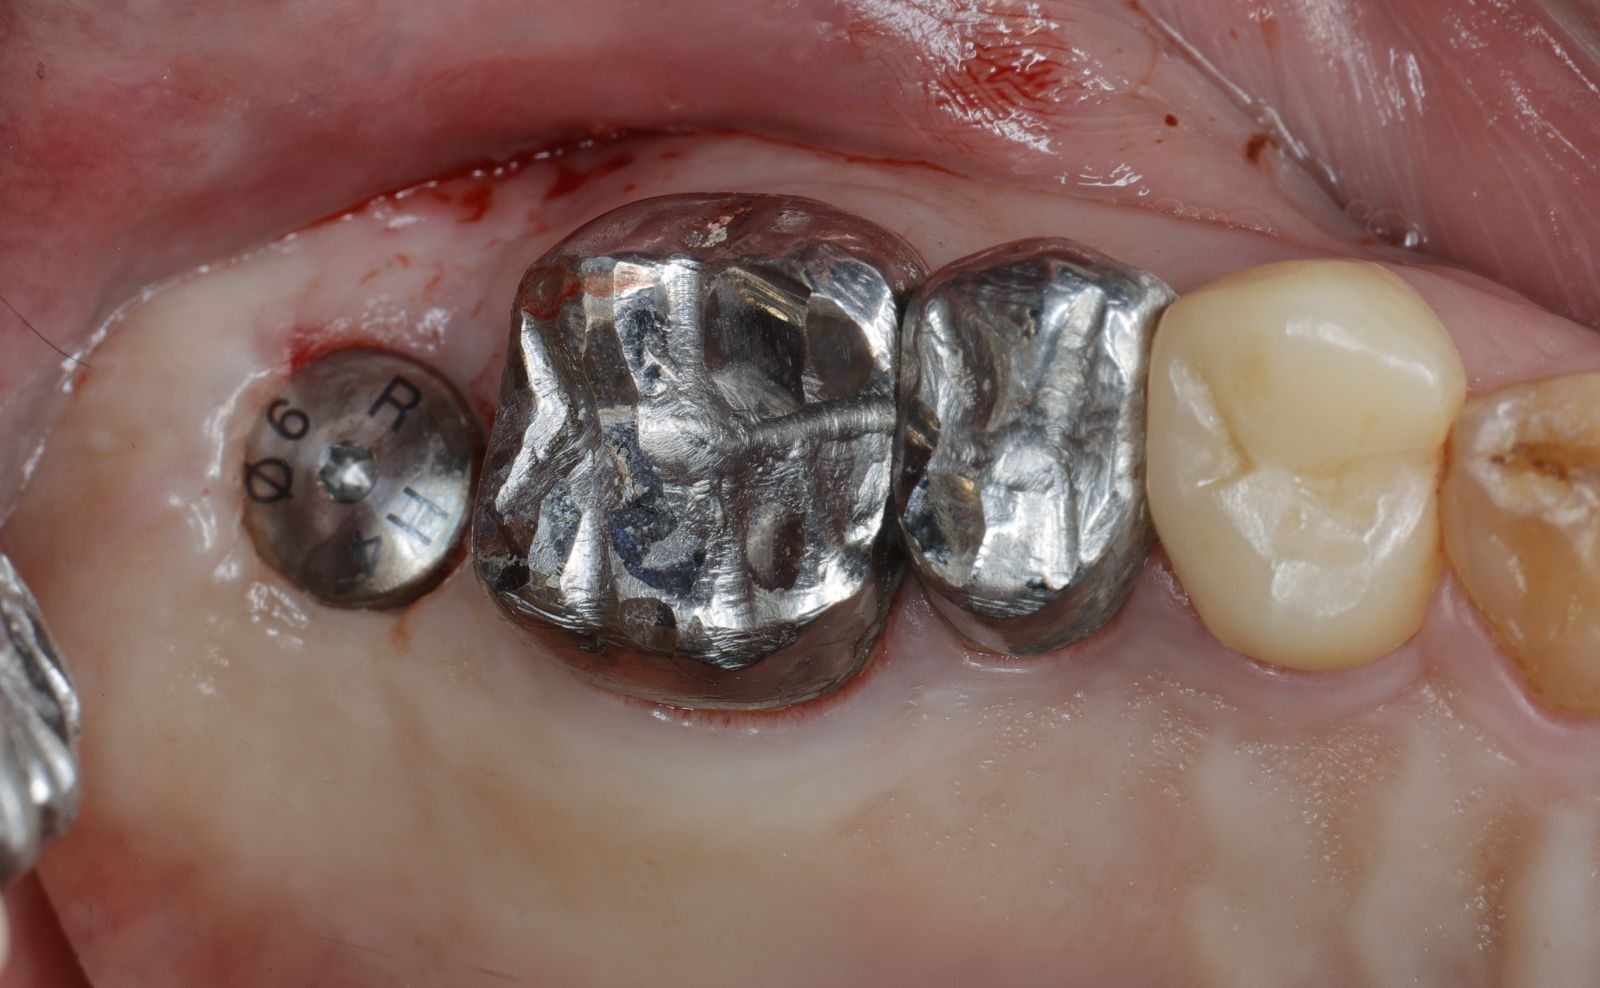

【 案 例 一 】

- 手術過程,在植入植體前先用導板定位,確認植牙位置及角度。

- 植牙當下不用劃開傷口無須縫合,鎖上癒合帽即可,也不需縫合傷口

待3.4個月後裝上全陶瓷牙冠完成植牙療程。整個療程過程輕鬆。